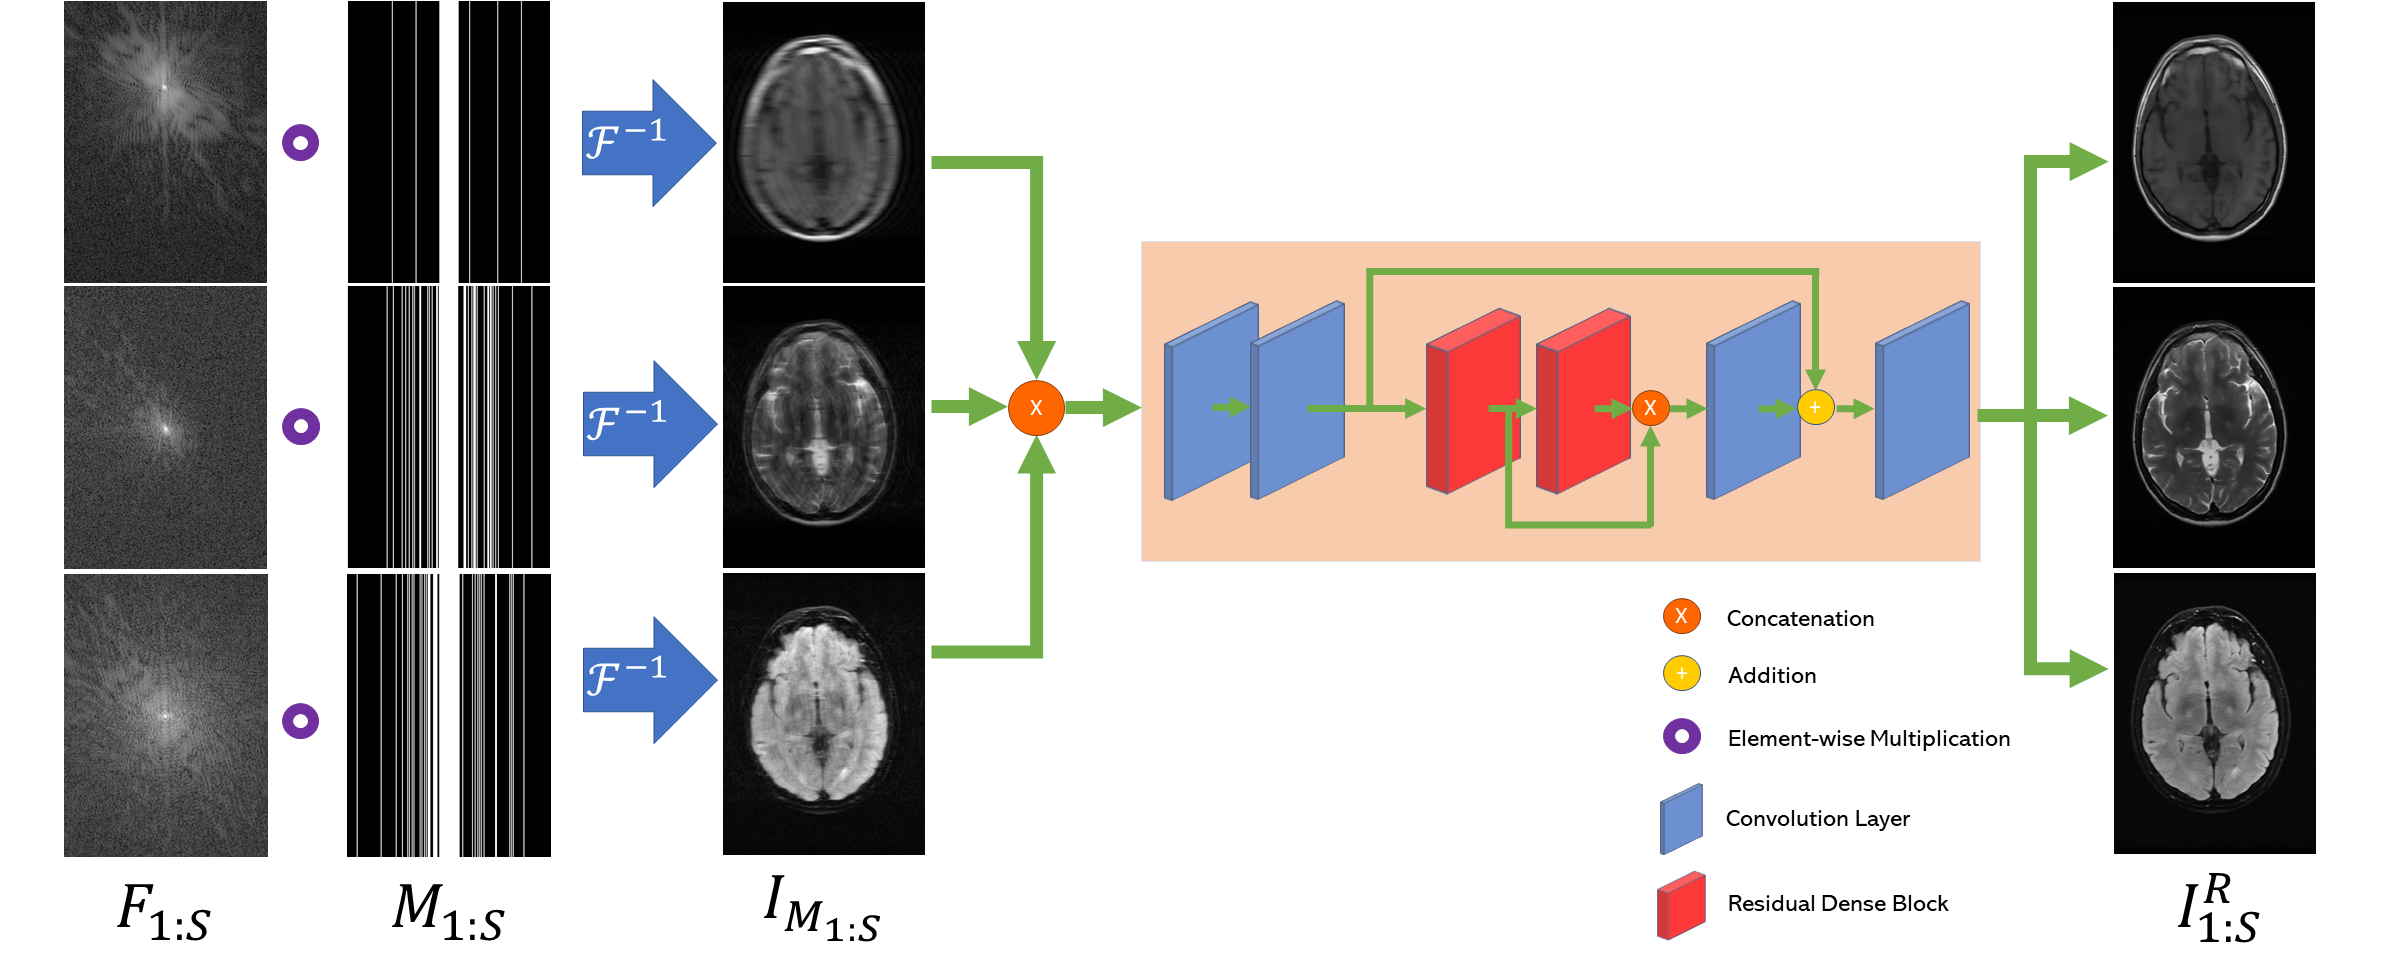

2.4 Network architecture

Our multi-sequence simultaneous recovery approach is shown in Fig 1. The approach is based on Residual Dense Block (RDB) [13], which incorporates the idea of residual learning and dense block [14], allowing all layers of features to be seen directly by other layers. During learning, each raw k-space data first gets undersampled through a randomly generated mask . The results are then transformed from k-space to image space, and concatenated before sent to the recovery network, which outputs . The loss function is defined as the following: .